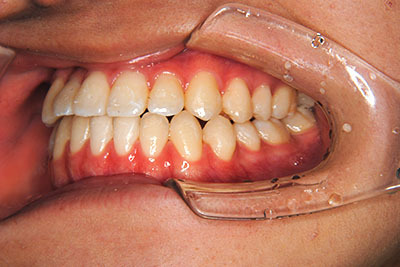

小学生高学年や中高生で矯正治療を考えている方へ

歯が乳歯から永久歯に生え変わった小学生高学年や、中高生でも矯正治療に手遅れということは全くありません。

成長中の顎の骨を矯正できたり、この時期の矯正はおとなになってから矯正治療を始めるよりも短期間で済むことがほとんどです。当院だとおおよそ1年で動的治療(マルチブラケット装置をつける期間)が終わることが多いです。